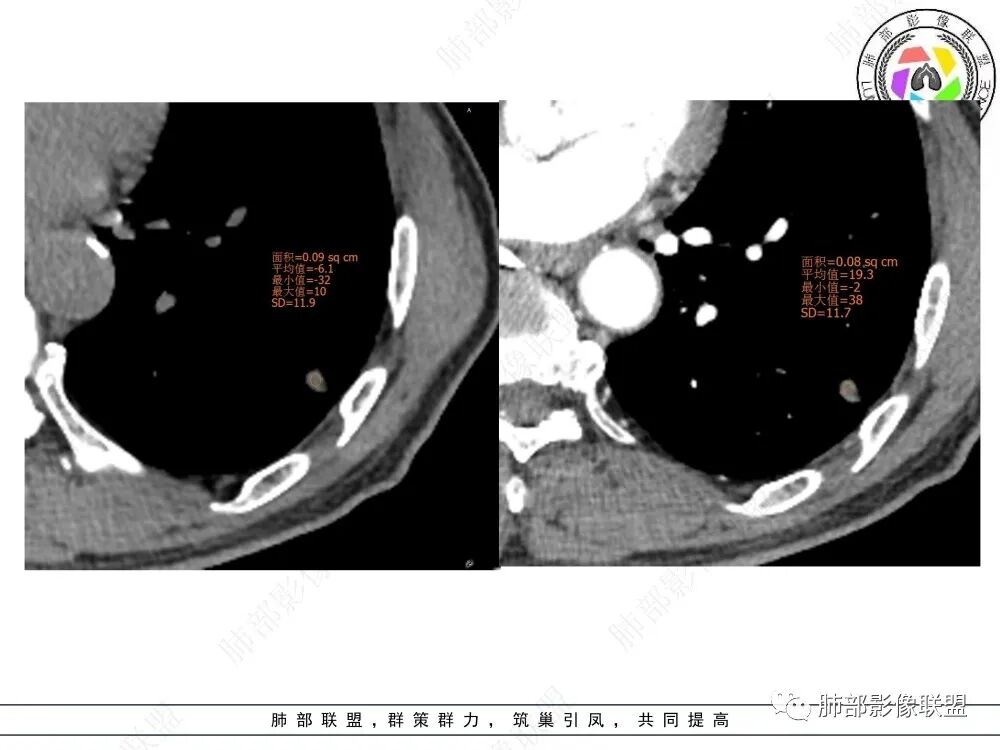

2、影像特点:左肺上叶尖后段病灶结合病史考虑消融术后改变,双肺下叶胸膜下可见多发大小不等的实性结节,周围似乎有晕,边缘平直为主,未见深分叶,部分可见邻近胸膜牵拉,张力不高,增强后呈轻中度强化。

(孤立肉芽肿型,本例为弱强化、增强内部未见血管影)

(本例为中度强化,增强可见血管造影征)